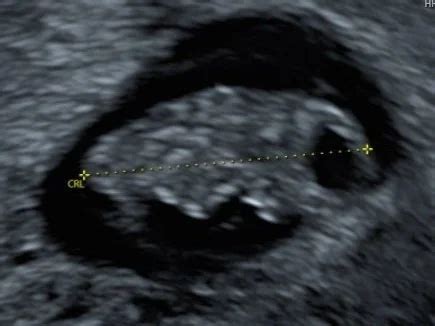

Een ander belangrijk aspect van de eerste trimester screening is de nekplooimeting. Tijdens een echo wordt de dikte van het vochtlaagje achter de nek van de baby gemeten. Bij de meeste foetussen met het syndroom van Down is deze nekplooi verdikt. Hoe dikker de nekplooi, hoe groter de kans op een afwijking. Het is echter belangrijk te weten dat bij meer dan de helft van de foetussen met een verdikte nekplooi na vervolgonderzoek geen syndroom van Down wordt gevonden.

De screening kan plaatsvinden vanaf de 11e week tot uiterlijk de 14e week van de zwangerschap. Specifiek voor de nekplooimeting geldt dat deze het meest duidelijk zichtbaar is tussen de elfde en veertiende week.

Echoscopie

Tijdens de echoscopie ligt de zwangere op een onderzoekstafel. Een professional gebruikt een apparaat dat, na aanbrengen van gel op de buik, geluidsgolven uitzendt die terugkaatsen van de foetus. Deze teruggekaatste golven worden omgezet in beelden op een monitor. Op basis van deze beelden, de grootte van de foetus en de analyse van de vrije ruimte, beoordeelt de arts de gezondheid van de baby.